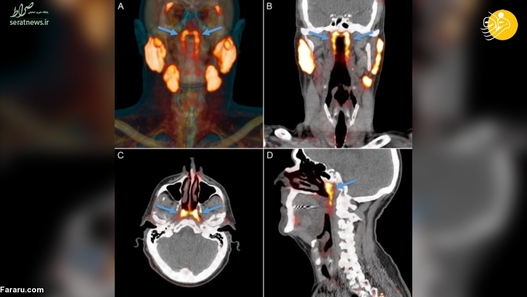

دانشمندان در موسسه سرطان هلند اعلام کردند که دو غده در جمجه سر، محل تقاطع حفره بینی و گلو، کشف کرده‌اند که احتمالا بخشی از سیستم غده‌های تولید کننده بزاق در بدن است. به گزارش فرارو، این محققان به طور اتفاقی هنگامی که برای درمان سرطان پروستات به اسکن غده‌های دیگر در بدن یک بیمار نگاه می‌کردند متوجه این دو غده شده‌اند. ‌ آنها سپس به اسکن 100 بیمار دیگر که سرطان پروستات داشتند نگاه کردند و وجود این دو غده را در بدن آنها هم تایید کردند. با این‌ حال پژوهشگران دیگر معتقدند این تحقیق تنها بر موارد محدودی بوده است که همه مرد و مبتلا به سرطان پروستات بوده‌اند و برای قطعیت وجود این دو غده باید بر روی بدن زن‌ها و شمار بیشتری از انسان‌ها هم تحقیق شود.